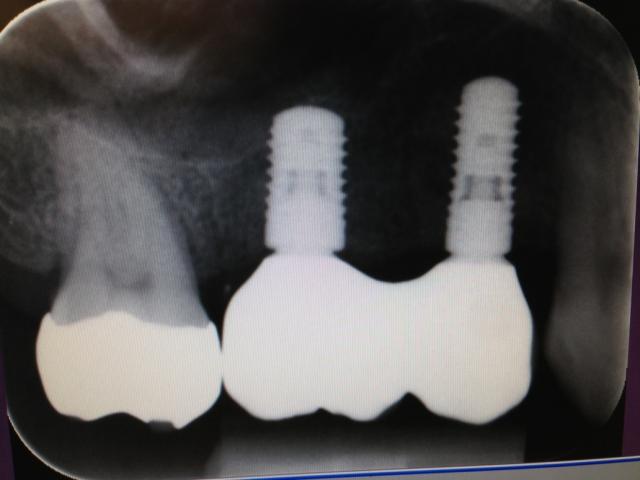

¥¤¥ó¥×¥é¥ó¥È¼´¤ò¤Ê¤ë¤Ù¤¯°ìÃ×

¥¤¥ó¥×¥é¥ó¥È¤Ï£²²óË¡¡Ê¥×¥é¥Ã¥È¥Õ¥©¡¼¥à¥¹¥¤¥Ã¥Á¥¿¥¤¥×¡Ë

¥¤¥ó¥×¥é¥ó¥È¤Ï£±²óË¡Íѡʥޡ¼¥¸¥óÉô¤Ï¹ü±ï¤è¤ê£²ÐÎ¥¤¹¡Ë